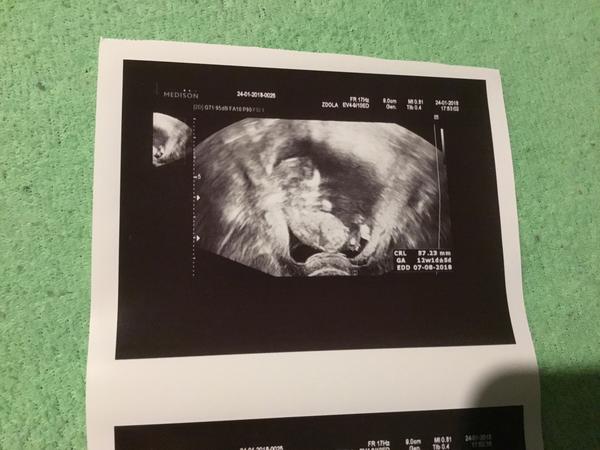

@lusen Mudr na screeningu taky říkala právě že je tak o tyden mladší, naměřila CRL 44 mm, moje gyn ale od začátku (7tt) říká, že velikost odpovídá a dnes mi to potvrdila, naměřila 53 mm. Na screeningu mi řekli, že ma vlastně úplně minimální rozměr pro to vyšetření, ale aby to udělali pořádně, tak že me preobjednaji. Byla jsem tam 11+4 a nové půjdu asi 12+6 nebo tak něco (dle PM) 🙂

Tak já jsem konečně po kontrole 🙂 Nakonec je miminko starší,než jsem myslela (10+6tt) a má skoro 4cm 🙂 Příští týden nás čeká 1.screening a 9.2. 5D UTZ kvůli genetice.